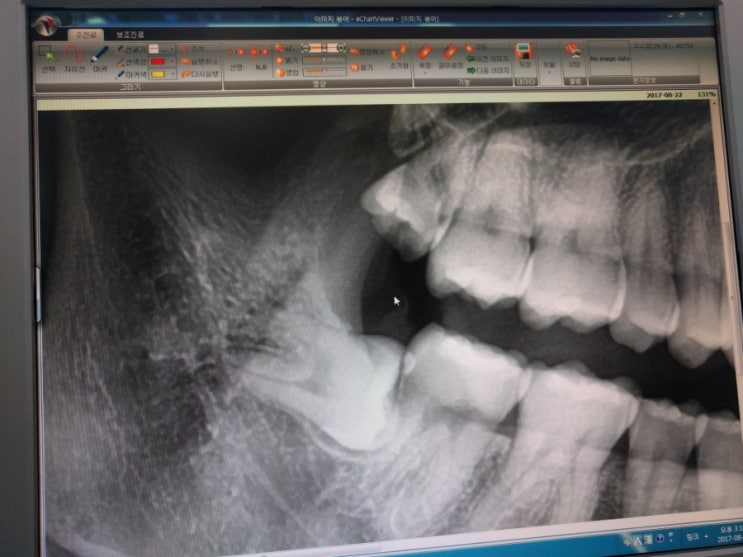

매복사랑니 발치하구나서..

사랑니 아래거 뺏지만 뿌리는 남아잇당 앞에만 잘개해서 드러내는 방식이다.. 흠.. 난 뱔로맘에안든다 돈이...